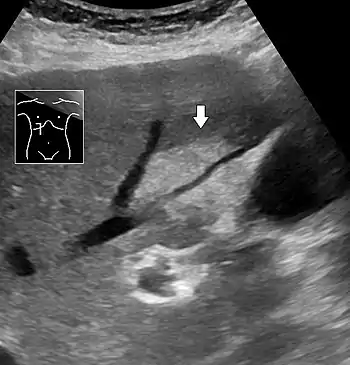

On abdominal ultrasonography, steatosis is seen as a hyperechoic liver as compared to the normal kidney.

Abdominal ultrasonography with the liver and kidney side by side (left image) may give a false impression of hyperechogenic liver, so it's preferably done with the organ borders facing the ultrasound probe (right image, of the same case).

Abdominal ultrasonography of focal steatosis. It is distinguished from a tumor by not compressing the hepatic vein.